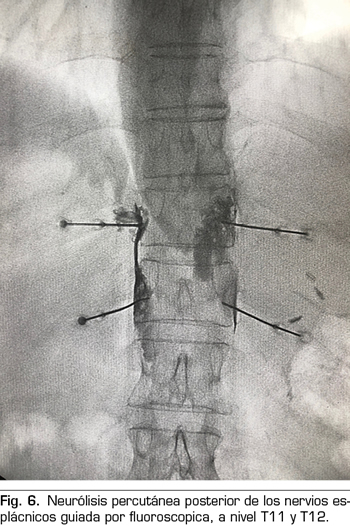

Se realiza mediante un abordaje posterior retrocrural, normalmente guiado por fluoroscopia (Figura 6). Las lesiones pueden llevarse a cabo mediante radiofrecuencia convencional o utilizando agentes neurolíticos como en el plexo celiaco.